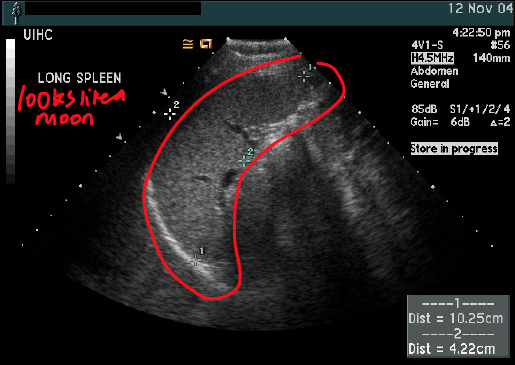

what are the dimensions of this spleen?

is this normal?

long 10.25cm

AP 4.22 cm

a bit small perhaps